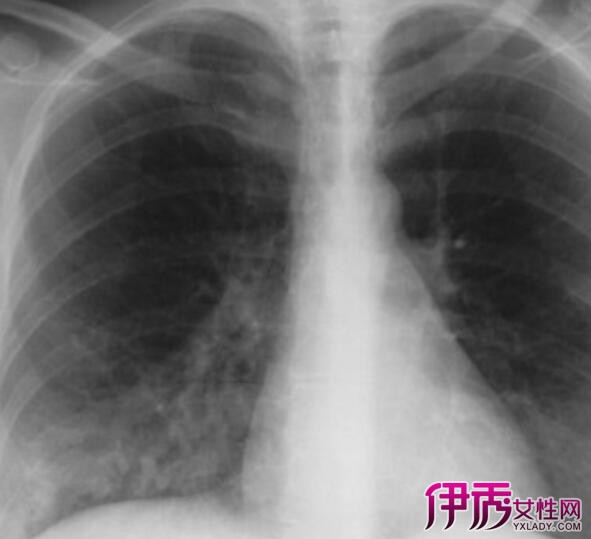

支气管炎可分为急性支气管炎和慢性支气管炎,均会伴有咳嗽,咳痰,喘息,呼吸困难等症状,发生急性支气管炎时应该及时治疗,否则会经过反复感染长期的刺激,可形成慢性支气管炎,患有支气管炎的患者应及时戒烟,适当的进行体育锻炼,锻炼时应选择不太激烈的项目,改善呼吸系统的功能,曾强对寒冷和疾病的抵抗能力!

由于咳嗽和气管炎都属于呼吸系统的疾病,如果在早期半声咳中得不到有效控制是可以造成长期性的半声咳!为了更好的控制早期半声咳,我们在饮食和生活习惯中应特别的重视,首先嘴中药的就是戒烟,90%的支气管炎患者都是因为长期的大量吸烟所引起的,如果戒烟之后你的支气管炎会逐渐改善,多喝绿浓茶并多注意避免刺激性的气体吸入!